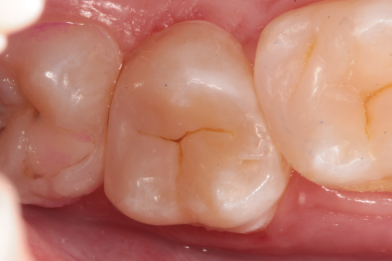

Лечение среднего кариеса 2.6. Функциональная и эстетическая реставрация зуба

Эвинян Лусине Артоевна -